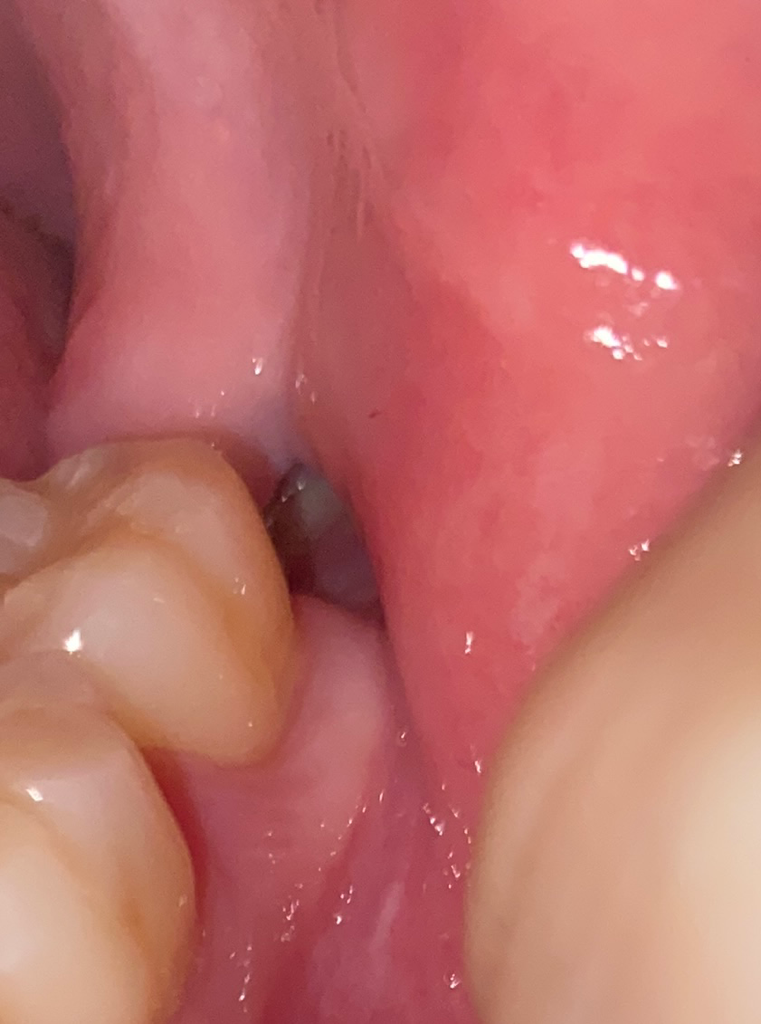

매복사랑니 뺀 곳 잘 아물고 있는 건가요?

매복사랑니을 뺏는데 잘 아물고 있는 건가요..?

3주차입니다

여기서 뽑을 땐 봉합을 안 해주셔서 저렇게 구멍이 그냥 나있어요..

안 쪽에 흰색도 보이고..ㅠ

구멍이 너무 큰 거 아닐까요...

잘 아물고 잇는거 같습니다. 하얗게 보이는건 잇몸이 치유되면서 생기는 현상이니 너무 걱정하지 않으셔도 됩니다.

사랑니를 발치한 부위는 사랑니가 기울어 나 있거나 하면 발치 부위가 큰 경우가 있습니다.

대부분 잇몸은 2주 정도 지나면 아물게 되며 잇몸 뼈는 3개월에 걸쳐서 천천히 치유가 되게 됩니다.

사진으로만 봤을 경우에는 큰 문제 없이 아물고 있는 것으로 보이나 주기적으로 치과에서 검진을 받아 보는 것이 좋습니다

사진상 특별히 문제가 보이지는 않습니다. 통증이 극심하거나 냄새가 나면 치과 가보시면 됩니다.

사랑니 빼고 나면 원래 구멍이 생기며 몇달이 지나면 스스히 차 오릅니다. 안쪽에 흰색은 정상적으로 아물고 있는 것으로 가장자리에 희게 딱지 앉은 것으로 보면 됩니다.